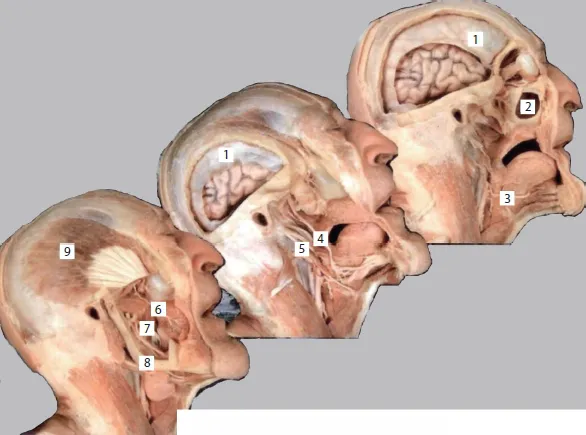

This comprehensive and exhaustive medical atlas of topographic and pathotopographic human anatomy is a fundamental and practically important book designed for doctors of all specializations and students of medical schools. Here you can find almost everything that is connected with the topographic and pathotopographic human anatomy, including original graphs of logical structures of topographic anatomy and development of congenital abnormalities, topography of different areas in layers, pathotopography, computer and magnetic resonance imaging (MRI) of topographic and pathotopographic anatomy. You can also find here new theoretical and practical sections of topographic anatomy developed by the author himself which are published for the first time. They are practically important for mastering the technique of operative interventions and denying possibility of iatrogenic complications during operations.

Topography and Pathotopography of the Head